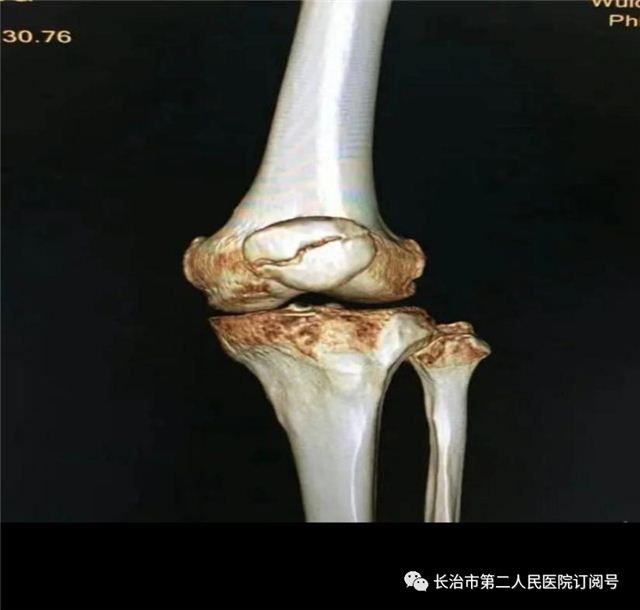

临床表现

临床处理